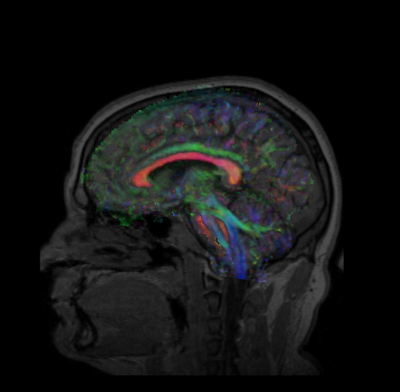

Develop a quick (< 10 min.) affine-based registration between multi-modality images for use in the AMIGO surgery suite. This module supports a fast registration using a small number of fiducials (3-5) and results in an accurately registered moving image. During this project week, we will refine the GUI and if necessary, complete work on the fiducial registration module in Slicer4.

Unregistered.png Fiducials-pre-registered.png FiducialsRegistrationResult.png